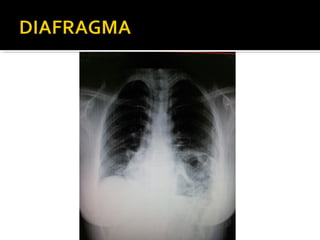

Este documento fornece parâmetros técnicos para realizar uma radiografia de tórax, incluindo posicionamento correto do paciente, dose adequada de radiação e estruturas anatômicas a serem avaliadas, como coração, pulmões, pleura, diafragma e ossos do tórax.